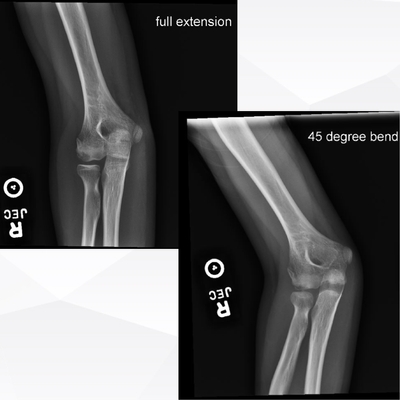

Click on an image below to view more info.